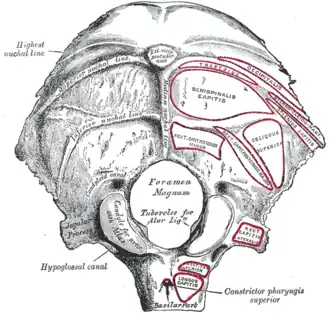

Occipital bone. Outer surface. (Condyloid canal visible at center left.) | |